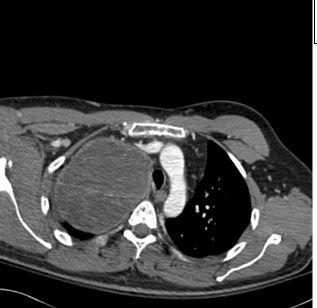

A 46-year-old man with a history of HIV infection presents to the emergency department for left flank pain. A lateral x-ray film of the patient’s lumbar spine is shown. What is the diagnosis?